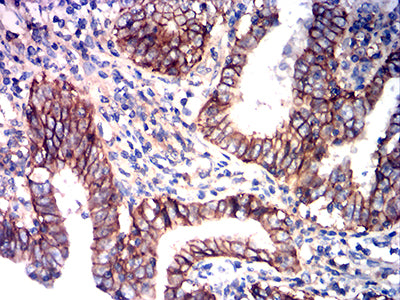

分类: 科研抗体货号: 31937别名: BSG; OK; 5F7; TCSF; EMMPRIN应用: IHC,FCM反应种属: Human